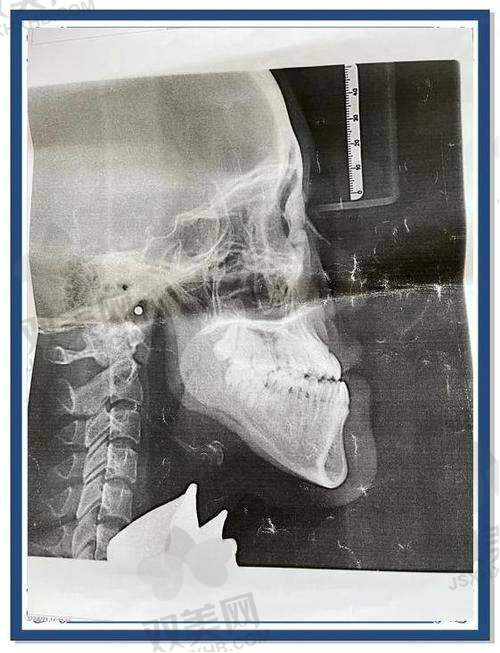

金柱翰医生擅长的项目可不少呢!在长沙华韩华美,他可是下颌角整形方面的一把好手。长沙华韩医疗美容医院专门邀请他来做高难度四级颅颌面整形手术。他在磨骨、颧骨颧弓内推、超长线下颌角截骨、下巴整形等领域有着超级丰富的整形外科经验。他就像一位神奇的雕塑家,能根据求美者的面部状况和身材比例,对面部进行精心整形,打造出更好看的脸部轮廓。他还主打“长曲线下颌角截骨”,这个术式不仅自然,而且修复还快,简直是想改善脸型的小伙伴们的福音啊!

金柱翰医生的技术特点十分突出。他在手术过程中就像一个精密的工程师,每一个操作都精细无误。在进行面部整形时,他会充分考虑到面部的整体协调性和美感,不会只追求单一部位的改变,而是让整个面部看起来更加和谐、自然。就拿他擅长的长曲线下颌角截骨来说,他能够巧妙地塑造出流畅的下颌线条,让术后的成效就像是天生的一样。而且他还特别注重细节,会在手术中尽量减少对周围组织的损伤,这样就能让求美者修复得更快,减少痛苦。